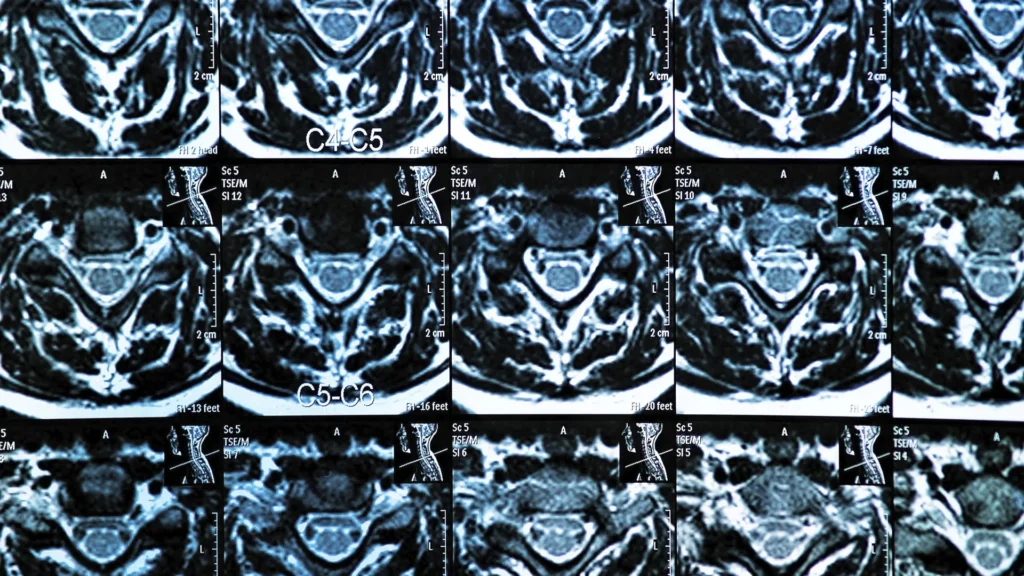

MRI trong lập kế hoạch phẫu thuật

MRI được sử dụng thường xuyên nhất để lập kế hoạch cho các ca phẫu thuật cột sống. Phim chụp này cung cấp hình ảnh chi tiết về các mô mềm, bao gồm đĩa đệm, dây thần kinh và tủy sống – những cấu trúc vốn không thể quan sát rõ trên X-quang hoặc chụp cắt lớp vi tính (CT scan).

- Nếu một khối thoát vị đĩa đệm đang chèn ép rễ thần kinh, MRI giúp phẫu thuật viên quyết định nên thực hiện lấy nhân đệm vi phẫu hay phẫu thuật nội soi.

- Trong các trường hợp hẹp ống sống nặng, MRI chỉ ra vị trí chính xác và mức độ hẹp, giúp phẫu thuật viên lập kế hoạch mở cung sống hoặc các quy trình giải ép khác.